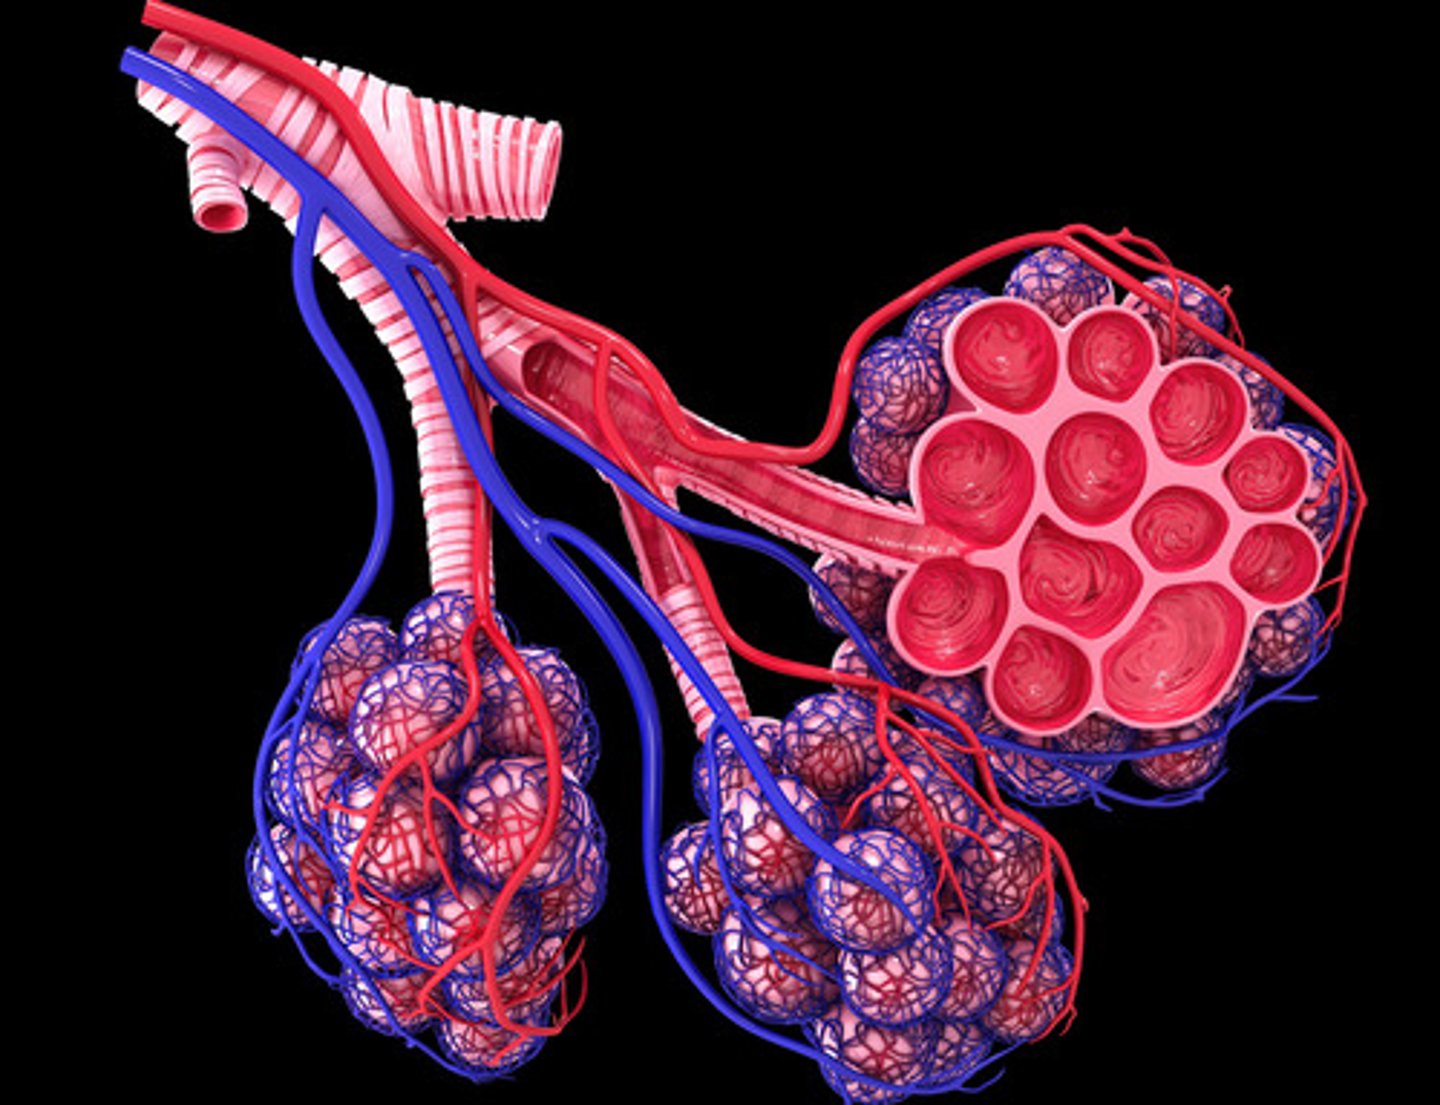

Primary bronchus

Secondary bronchi

Any of the tertiary bronchi

Bronchioles

Alveoli

Pulmonary arteries

Pulmonary veins